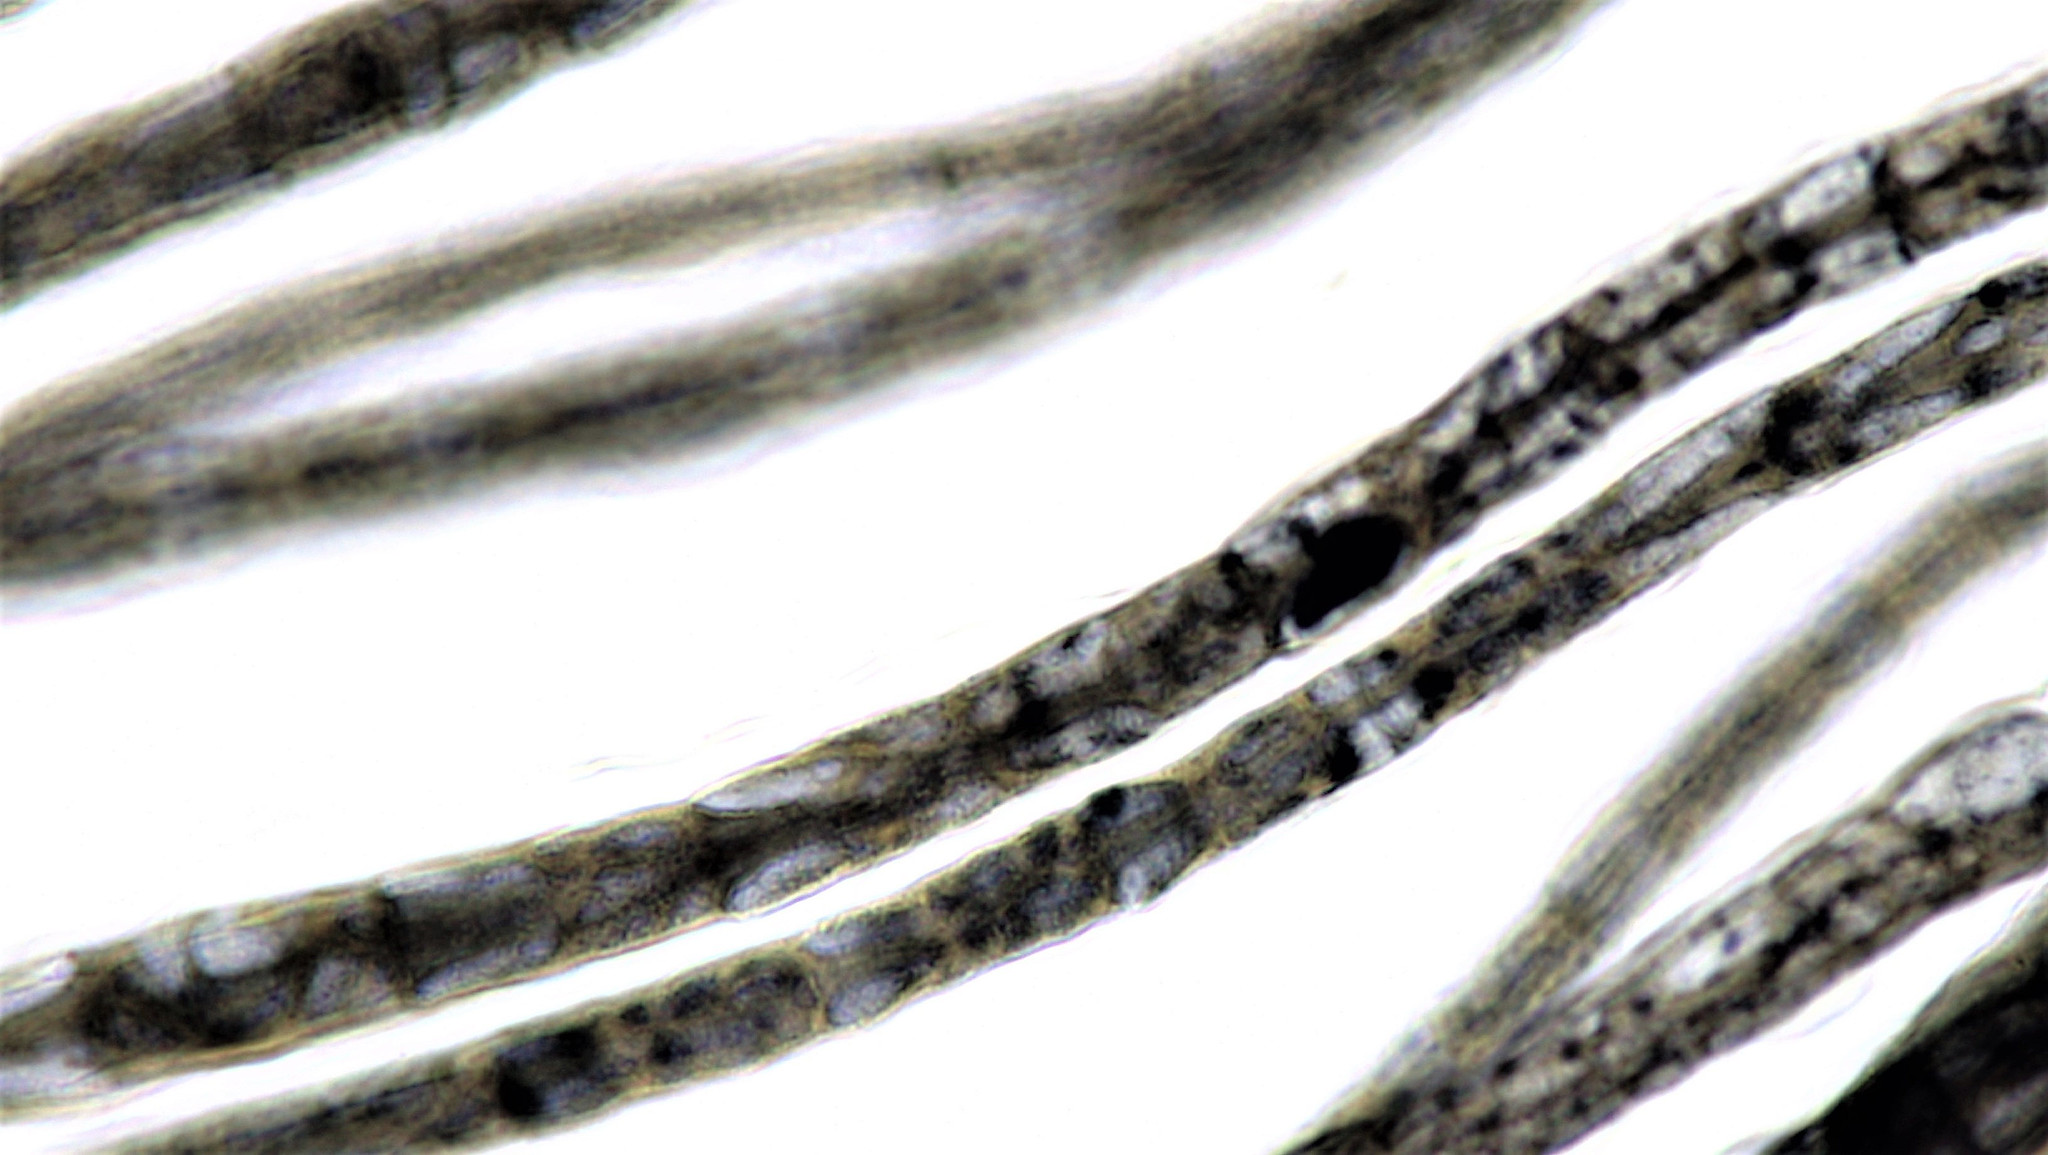

The researchers noted the drug had similar effects on nerve cells as those observed in drugs like ketamine, LSD, MDMA and DMT.

The researchers noted the drug had similar effects on nerve cells as those observed in drugs like ketamine, LSD, MDMA and DMT.

The researchers suspect the synthetic psychedelic changes the neutrons in brain circuits associated with depression, anxiety, PTSD and addiction, and that it may prove to be a multipurpose breakthrough drug for treating some of the most intractable conditions plaguing humanity.